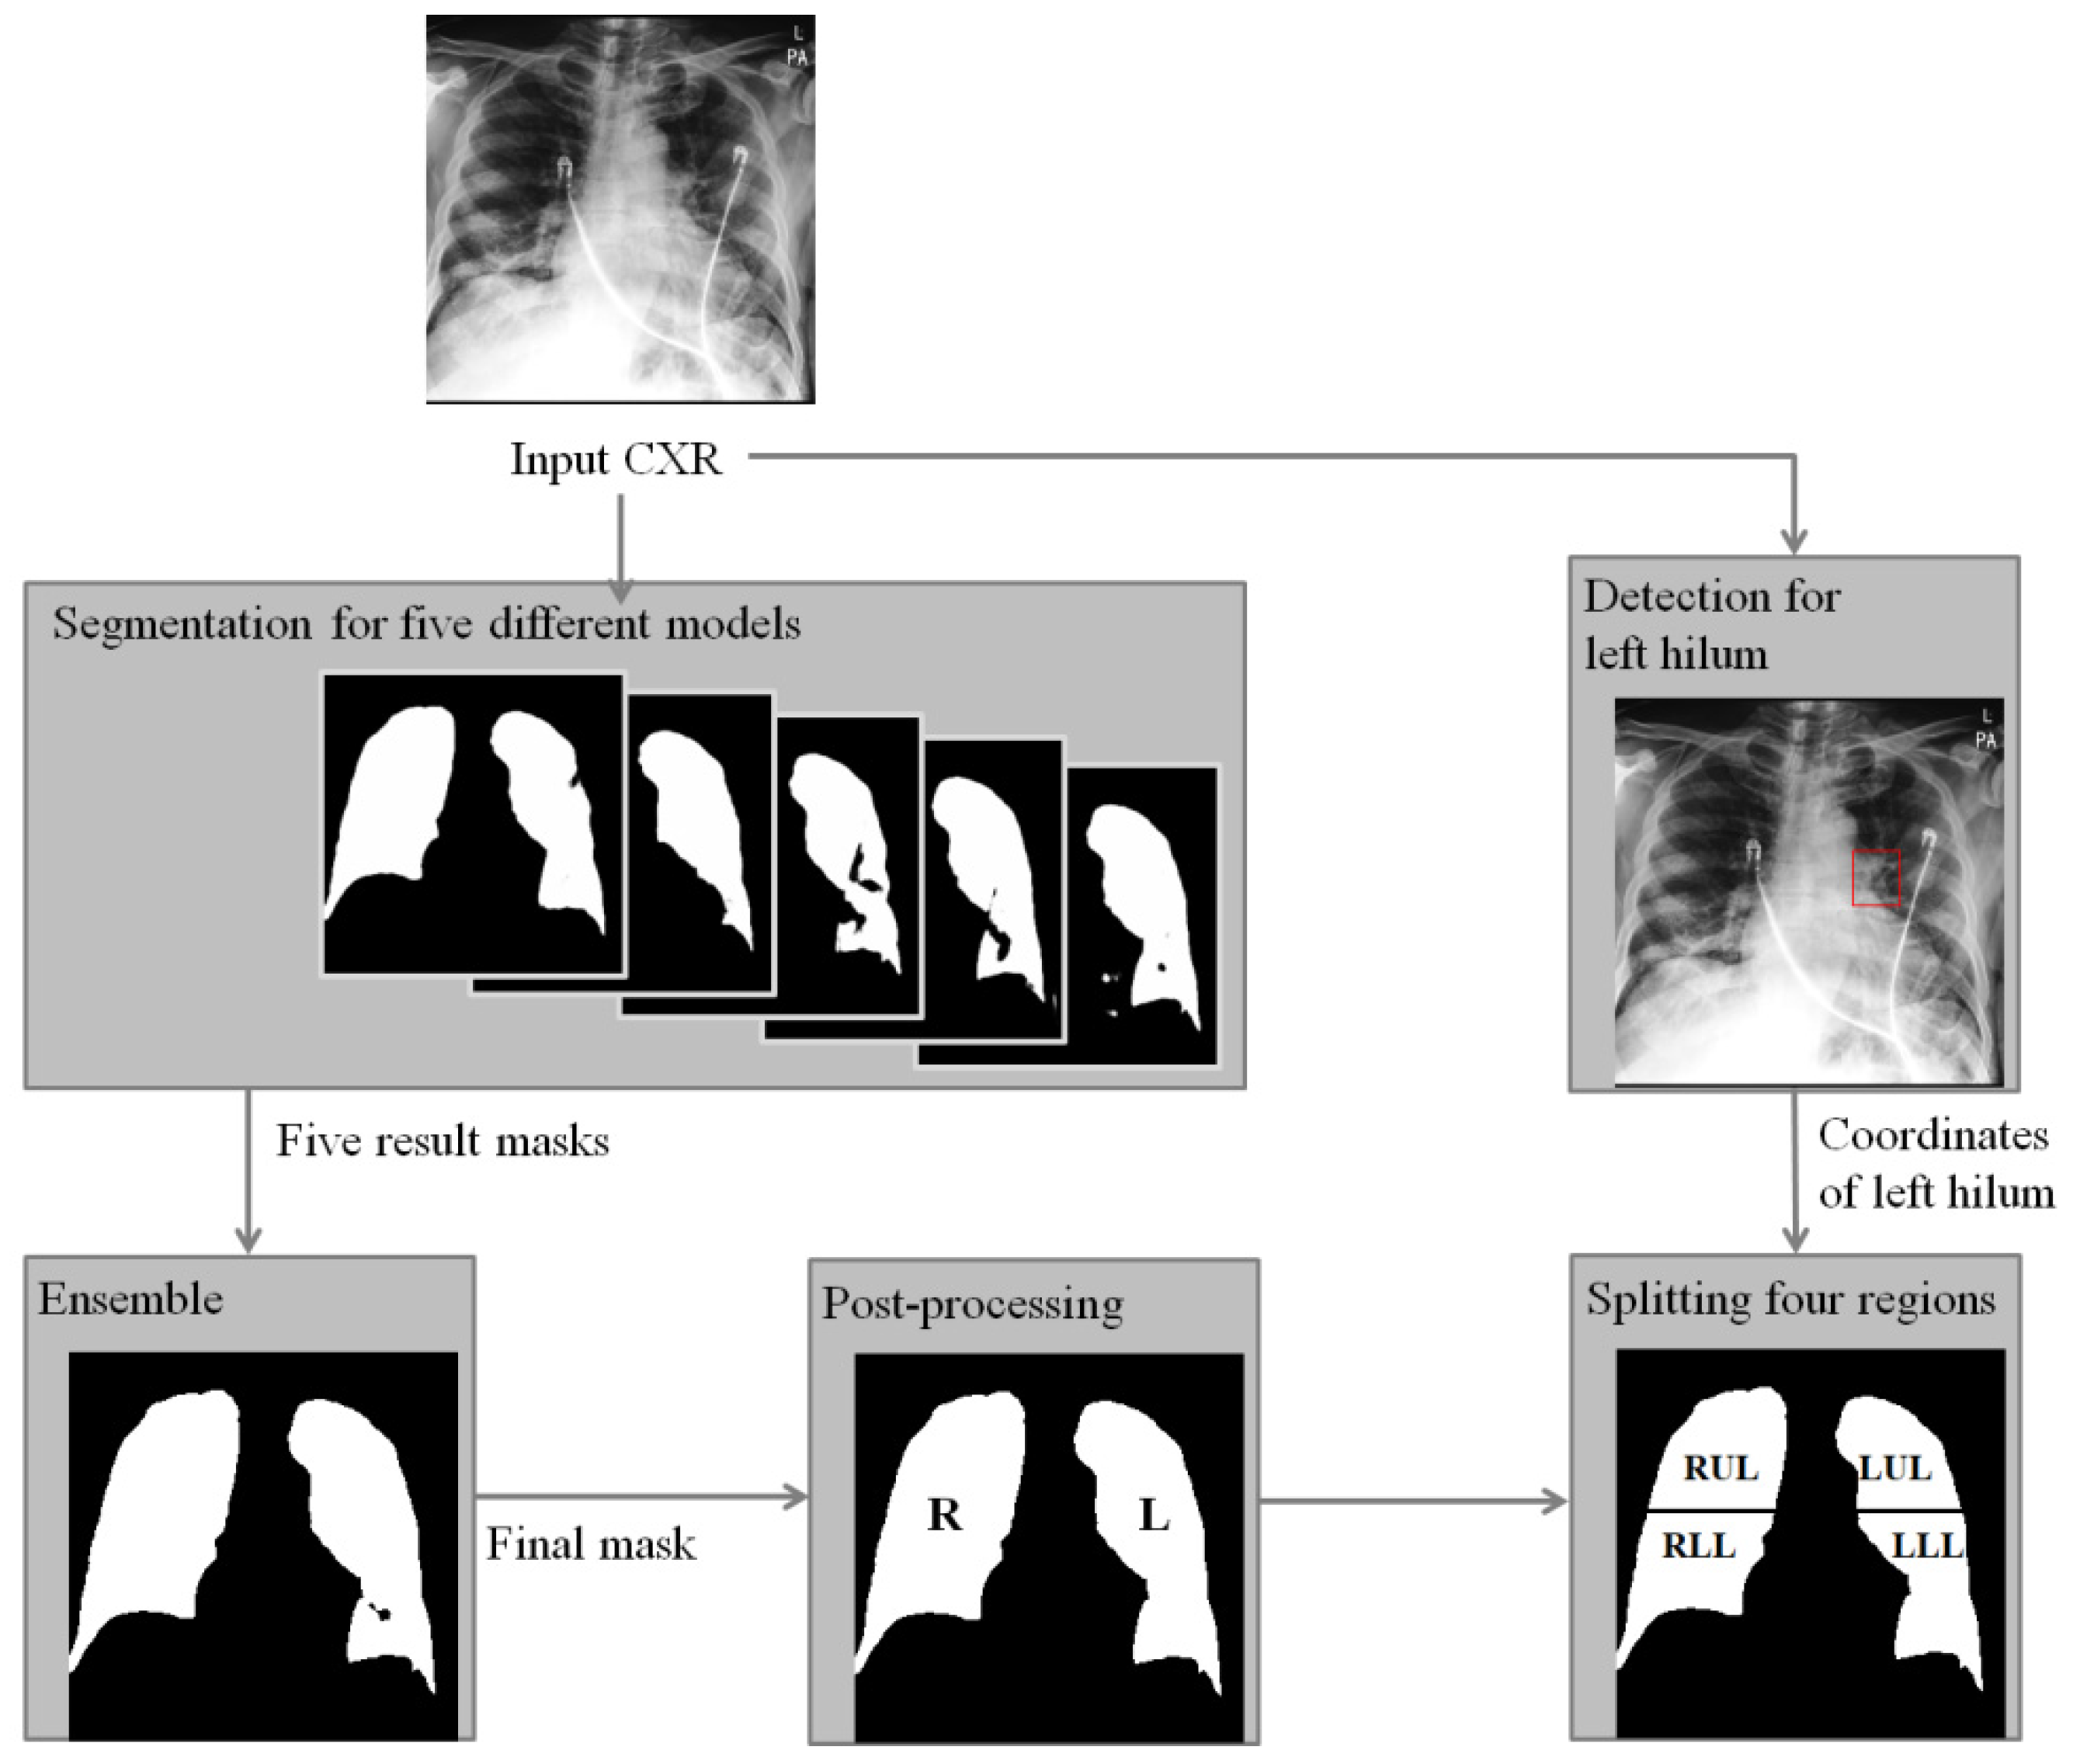

Diagnostics Free FullText Deep LearningBased FourRegion Lung

Diagnostics Free FullText Deep LearningBased FourRegion Lung Covid Chest X Ray Dataset Github  There are 517 cases of covid. We also introduce covidx, an open access benchmark dataset that we generated comprising of 13,975. Covidx dataset | papers with code. Covid Chest X Ray Dataset Github.